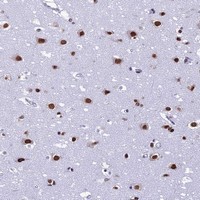

- Immunohistochemical staining of human cerebral cortex with PRAMEF12 polyclonal antibody (Cat # PAB24097) shows strong nuclear positivity in neuronal cells at 1:50-1:200 dilution.

- Immunohistochemistry (Formalin/PFA-fixed paraffin-embedded sections)